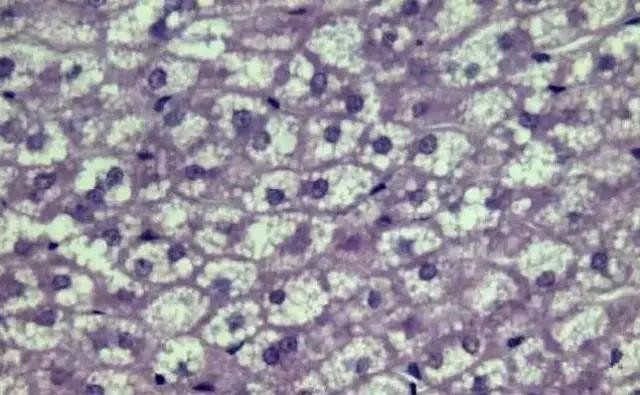

“ 镜下脂肪滴

“ 脂肪变性

“ 肝脂肪空泡